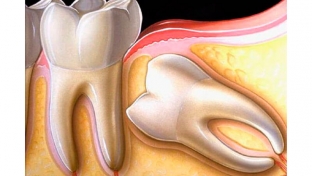

Неправильне положення зуба у зубному ряду називається дистопією. Дистопований зуб може бути зміщений за межі альвеолярного відростка щелепи. Таке становище зуба ускладнює прорізування і зростання сусідніх зубів, крім того, створює значний косметичний дефект. Найчастіше дистопованим зубом виступає третій моляр («зуб мудрості»), верхні та нижні ікла.

Досить часто дистопованими зубами є ікла та зуби мудрості. Чому саме ці зуби знає estet-portal.com. Це пов'язано з тим, що до моменту появи іклів у зубному ряду для них не залишається місця в зубному ряду, що змушує їх рости не на своєму призначеному місці. Зуби мудрості часто виявляються дистопованими через те, що вони не мають попередників, і їм самим доводиться проростати крізь кісткову тканину.

Дистопований зуб приносить, крім естетичних проблем, функціональні порушення. У деяких випадках дистопований зуб може виявлятися в тілі або гілки нижньої щелепи, у стінці порожнини носа, очниці або у твердому небі.

Дистопований зуб заважає нормальному прорізуванню зубів, що сприяє розвитку неправильного прикусу. До того ж, дистопований зуб пошкоджує та травмує тканини губ, язика та щік, що закінчується формуванням декубітальних виразок.